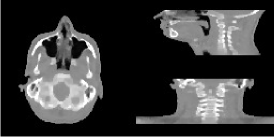

The data set we are using is derived from repeat CT scans of a neck cancer patient from the Cancer Image Archive [17][18]. With these, we will use the first CT scan as the planning image, then synthesise CBCT measurements on the follow up after 5 months—these are shown in Figures 3(a) and 3(b) respectively. A strong advantage of using this approach is that one has access to a ground truth, against which one can perform valid quantitative assessments.

Refer to caption

(a) Oracle image

(b) Planning image

(c) Registered plan

Figure 3: Experimental data used: (a) is the oracle follow-up CT image; (b) is an unregistered initial planning image; and (c) is the plan registered rigidly onto an FDK (with SKS correction) reconstruction of the raw data—shown is the high dose, but a separate registration was used in low dose.